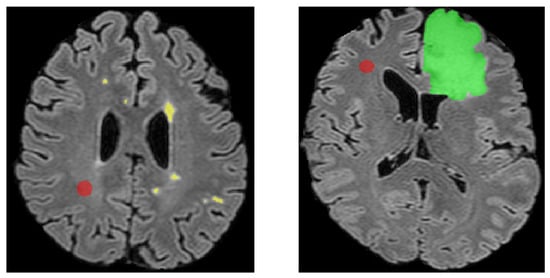

2.4.2. Single Component Abnormal Volume Evaluation

- “Found” (DSC ≥ 0.5): A threshold of 0.5 is frequently used as a minimum for meaningful overlap, as it indicates that at least half of the volume of a segmented region matches the ground truth. This threshold has been applied in tumor segmentation tasks, including challenges like BraTS (Brain Tumor Segmentation) and LiTS (Liver Tumor Segmentation), to identify valid detections where segmentation reasonably approximates the expert annotations [31,32].

- “Partially Found” (0.05 ≤ DSC < 0.5): The range from 0.05 to 0.5 accounts for partial matches where detection may overlap the GT but insufficiently to qualify as a reliable segmentation. This category acknowledges borderline cases that may provide some utility, for instance, hinting at the presence of a lesion but failing in detailed segmentation.

- “Missed” (DSC < 0.05): A DSC below 0.05 indicates negligible overlap, typically attributed to false negatives or detections that do not align meaningfully with the GT. Such cases are considered failed attempts to segment the target correctly.

2.4.3. Volume, Positional, and Intensity Analysis